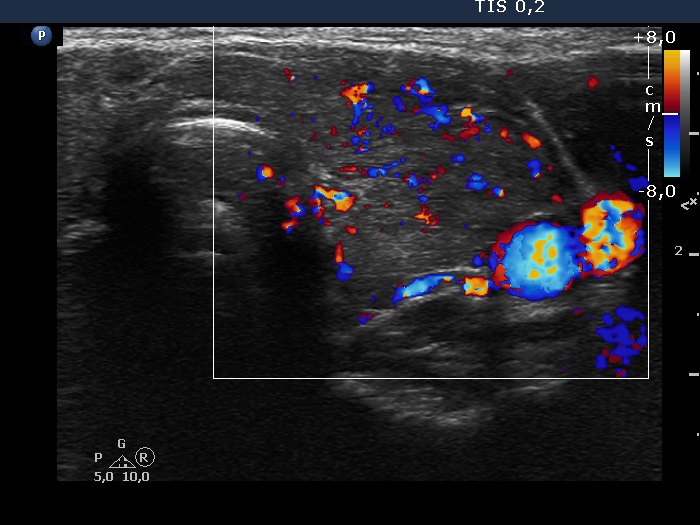

Graves' disease - case 1584

Four years after the first visit (ultrasonographic picture 7)

Right lobe, longitudinal scan

Left lobe, transverse scan. The vascularity became a bit increased.